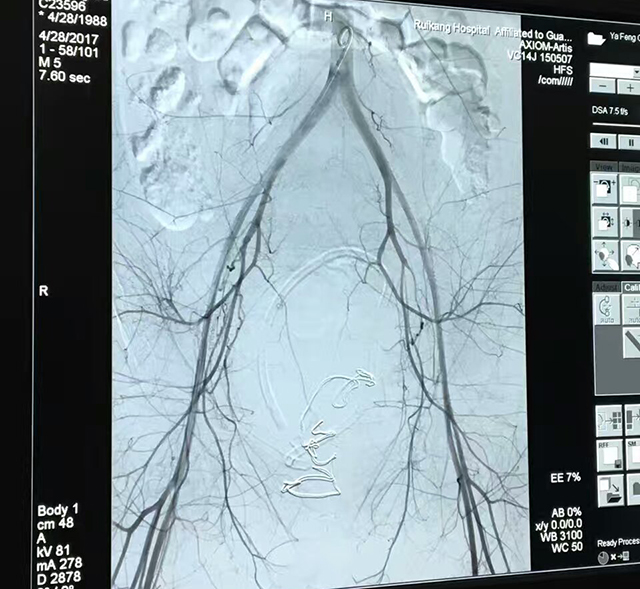

玉华医生介绍,牙女士在4月28日12点16分通过剖宫产分娩出一健康男孩,但由于子宫收缩欠佳,出现了术后大出血的状况。病情严重而紧急,产科苏莉主任立即组织医疗团队及其他相关部门联合抢救。抢救期间出血状况虽得到控制但仍出现几次反复,最后在介入科的共同努力下行子宫动脉栓塞+双侧髂内动脉栓塞术才终止了出血状况,抢救成功。牙女士在抢救八个小时后转危为安。

玉医生介绍,这是瑞康医院产科首次运用子宫动脉栓塞术成功治疗了难治性产后出血,这种新的介入治疗技术可应用在很多妇产科疾病中,尤其对产后出血、前置胎盘出血、瘢痕妊娠等临床棘手的、高风险的疾病,损伤小,止血效果确切肯定,既避免了二次手术的危险性,又能为患者保全子宫,保留生育能力。

目前针对产后出血的救治的方法有传统的按摩压迫子宫、加强子宫收缩药物、各种缝合,甚至子宫切除等,近年来成功运用子宫动脉栓塞术,髂内动脉栓塞术等技术到产后出血的救治中,疗效显著,逐步成为治疗难治性产后出血的核心技术。

介入治疗